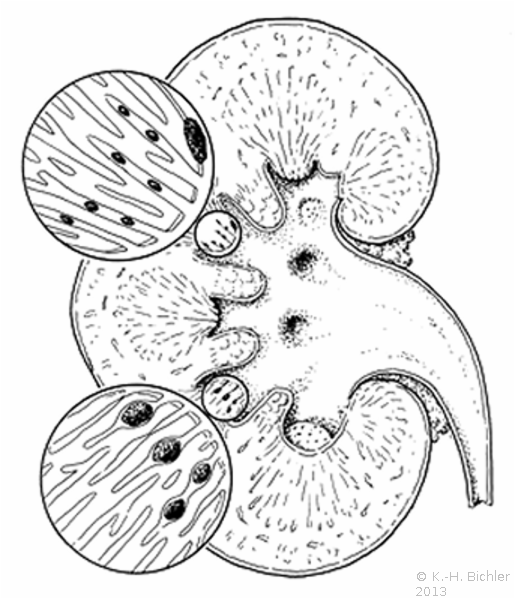

Literatur:http://www.bundesaerztekammer.de/page.asp?his=1.120.121.1042.5974; Leitlinie zur Qualitätssicherung in der Röntgendiagnostik: Qualitätskriterien röntgendiagnostischer Untersuchungen; Bundesärztekammer Stand: 23.11.2007. Sie schreibt das Verwenden von umschließenden Hodenkapseln, Ovarienabdeckungen und Bleigummiabdeckungen für den an das Nutzstrahlenfeld angrenzenden Körperbereich vor (

10 Abbildungen).